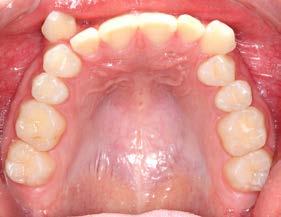

Se observa dentición permanente, 28 dientes erupcionados, el canino

superior derecho y el canino superior izquierdo se encuentran en una posición ectópica, líneas medias dentales no se pueden determinar por mordida cruzada, forma de arco superior e inferior elipsoidal, clase I

molar bilateral y clase canina no se puede determinar por la posición de los mismos. Presenta crecimiento horizontal con retroinclinación de incisivos superiores (Figura 2).

A nivel radiográfico podemos observar densidad ósea uniforme, la presencia de 4 gérmenes dentarios correspondientes a los terceros molares y una relación corona-raíz 2:1. Se puede observar el patrón de crecimiento horizontal (Figura 3).

En la radiografía lateral de cráneo mediante la cefalometría de Steiner podemos observar que es un paciente con crecimiento horizontal ya que presenta un ángulo Go-Gn / SN de 28°, un ANB de -4°, podemos observar que el SNA está reducido, lo que nos da el efecto de un maxilar retraído (Figura 4).